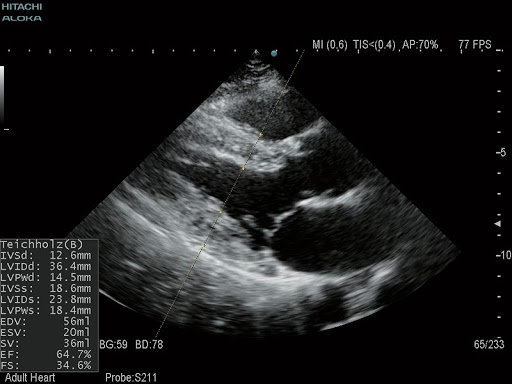

- Автоматическая оптимизация В-режима, допплеровского спектра и скорости ультразвука одним нажатием

S211 – Секторный фазированный датчик для проведения эхокардиографических исследований взрослых.